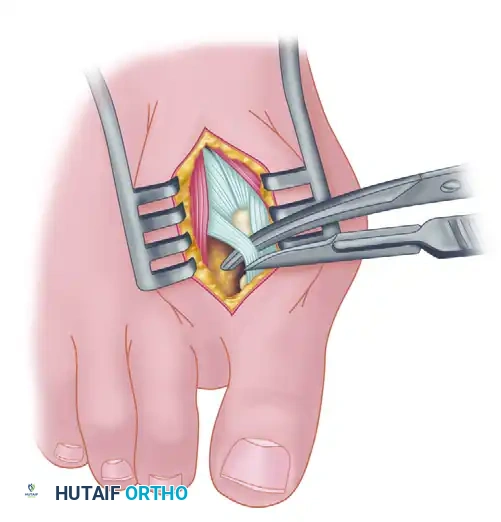

Adductor Tendon and Lateral Capsular Release

The lateral release is the biomechanical heart of the Modified McBride procedure. It mobilizes the tethered lateral structures, allowing the sesamoid apparatus to reduce beneath the metatarsal head.

- Begin the second stage with a dorsal longitudinal incision. Start 2 to 3 mm proximal to the dorsal aspect of the first web space to avoid postoperative web contracture. Extend the incision proximally between the first and second metatarsal heads for 3 to 4 cm.

- This approach provides adequate exposure of the adductor hallucis insertion into the base of the proximal phalanx, the lateral head of the flexor hallucis brevis (FHB) muscle converging on the fibular sesamoid, and the entire lateral capsule.

- Delicate retraction of the skin exposes the dorsal digital branches of the veins, which should be cauterized. Be highly vigilant for the terminal branches of the first dorsal intermetatarsal artery, which may be encountered adjacent to the proper digital branches of the deep peroneal nerve supplying the first web space.

- The main portion of the adductor tendon inserts into the base of the proximal phalanx just plantar to the longitudinal axis of the phalanx. It also possesses a smaller insertion, confluent with the lateral head of the FHB, into the fibular sesamoid.

Surgical Technique Tip: To easily identify the insertion of the adductor hallucis tendon, place a small, pointed, curved hemostat on the dorsolateral base of the proximal phalanx. Slide it firmly plantarward, then lift the hemostat dorsally and laterally. The tip of the instrument will reliably rest in the axilla of the adductor tendon insertion.

- Once the primary insertion is released from the proximal phalanx, grasp the tendon with a hemostat. Apply traction and displace it dorsally and laterally toward the second metatarsal.

- Spread the first and second metatarsal heads using a small Inge retractor or a Weitlaner retractor. Holding the adductor tendon under tension greatly facilitates deep exposure. The lateral head of the FHB, the lateral border of the fibular sesamoid, and the conjoined slip of the adductor tendon will come into clear view.

- Sever all attachments of the adductor into its conjoined insertion with the lateral head of the FHB into the fibular sesamoid. When fully released, traction on the adductor should result in free, independent movement without tethering the fibular sesamoid.

- Next, address the deep transverse intermetatarsal ligament, which lies just plantar to the adductor. Release this ligament carefully.

- Critical Pitfall: Release of the deep transverse metatarsal ligament severely endangers the neurovascular bundle to the first web space, which lies immediately beneath it. Slide a small Freer elevator between the ligament and the neurovascular bundle to protect these structures before incising the ligament. Following this, complete the lateral capsulotomy.